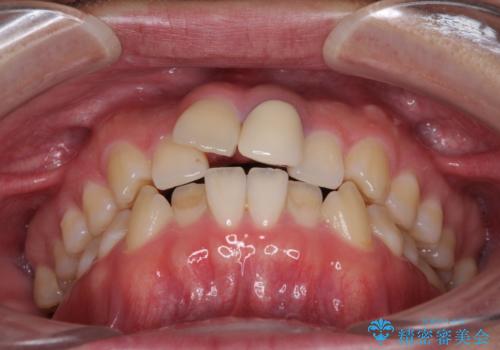

前歯の歯並びとクラウンを改善 インビザラインとオールセラミック

- 前歯の歯並びと不自然な色をした前歯のクラウンを気にして来院された患者様です。

上下前歯の歯列不正はインビザラインにより歯列を整え、その後に、前歯をオーダーメイドタイプのオールセラミッククラウンにて補綴治療することとしました。

初診時には、歯並びを整えることのみを検討されていましたが、歯列が整うにつれて不自然な色合いが気になるようになり、矯正治療を行ってから補綴治療をする計画を受け入れてくださいました。

口元の印象が明るく変わり、患者様には大変満足していただきました。